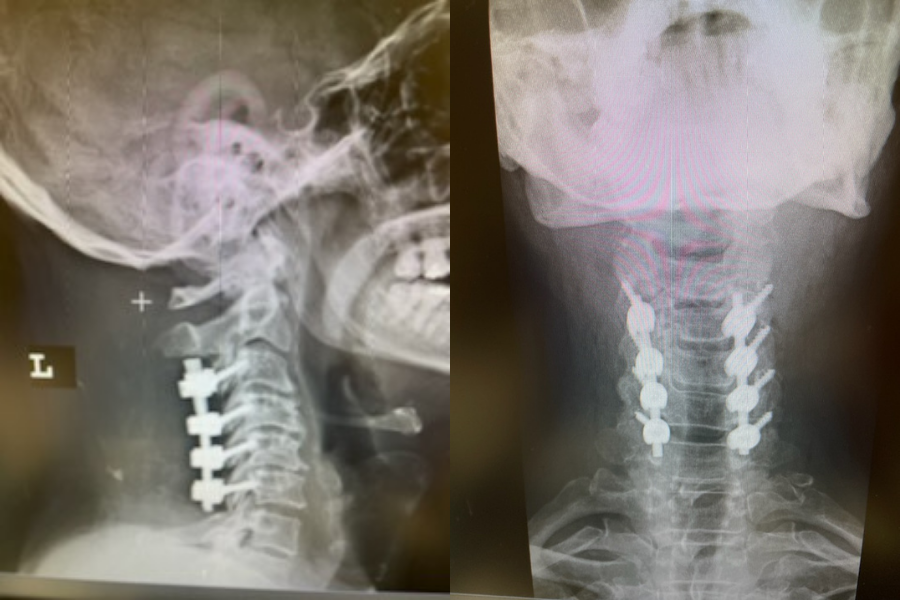

This 57 year-old male presents with severe neck, left shoulder and arm pain and weakness in his hand since being involved in a motor vehicle accident nine months prior. The patient had subsequent left shoulder surgery although he still complained of pain postoperatively and his weakness persisted. He was on no blood thinners. He underwent imaging. The cervical spine MRI revealed an extensive dorsal epidural collection from C1-2 through C5 with associated spinal cord compression. In addition there were multisegmental degenerative changes with foraminal stenosis worse at C4-5 (Fig. 1a and 1b).

(1a) Sagittal and axial T2-weighted cervical MRI demonstrating extensive dorsal epidural collection with hyperintense signal consistent with fluid causing spinal cord compression.

(1b) Hyperintense signal (arrow) at the C3-4 interspinous space consistent with ruptured interspinous ligament,C4-5 (Fig. 1a and 1b).